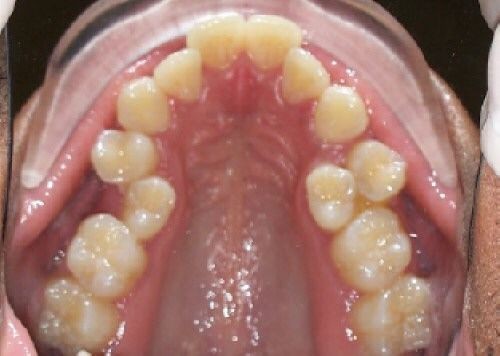

Dentist in porur Kids Dentist in porur cosmetic dentistry in porur If milk (primary) teeth are removed too early, it can lead to several issues with dental and jaw development, as these teeth play a key role in guiding the alignment of permanent teeth and supporting normal jaw growth. Here are some potential effects: 1. Misalignment of Permanent Teeth: Milk teeth act as placeholders for the adult teeth that will eventually replace them. If they are removed early, neighboring teeth may drift into the open space, potentially leading to crowding or improper alignment when the permanent teeth come in. 2. Delayed Eruption of Permanent Teeth: Sometimes, early removal of milk teeth can cause a delay in the eruption of permanent teeth. This happens because the teeth are no longer being naturally guided into place by the baby teeth. 3. Speech and Chewing Problems: Milk teeth aid in speech development and proper chewing. If they’re missing, it might affect a child's ability to chew or pronounce certain sounds. 4. Jaw Development Issues: Early loss of milk teeth can affect the development of the jaw, potentially leading to bite issues or the need for orthodontic treatments later. To prevent complications, dentists sometimes recommend using space maintainers to keep the area open for the permanent tooth if milk teeth need to be removed due to decay or damage. #cosmeticdentistporur##rootcanaltreatmentinporur##dermatologistinporur##Urologistunporur##generalphysicianinporur##Neurologistinporur##Gynaecologistinporur##